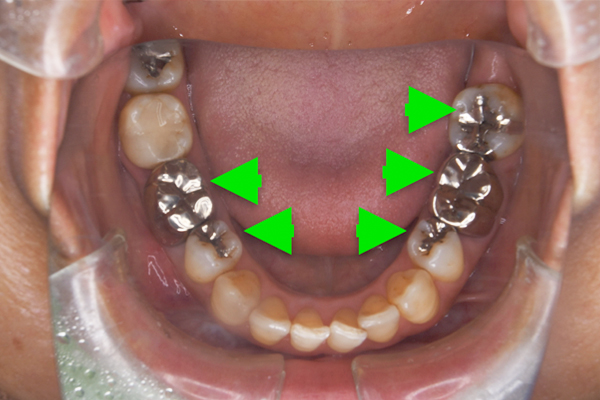

![]() |

|---|

| 主 訴 | 金属の見ためを改善したい |

|---|---|

| 治療期間 | 約2ヶ月 |

| 治療費 | セラミックインレー2本、 オールセラミッククラウン2本 511,500円(税込) |

| 治療内容 | 古い金属を見た目が自然で、虫歯にもなりにくいセラミックで治療しました。 |

| 治療上のリスク | 仮歯の間は噛み合わせに違和感を感じる場合が あります。 セラミックは稀に欠ける場合があります。 |